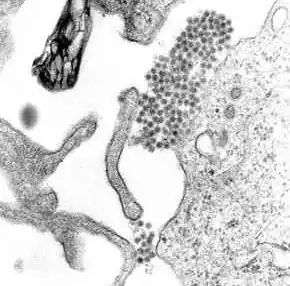

| A TEM micrograph showing dengue virus virions (the cluster of dark dots near the center) | |